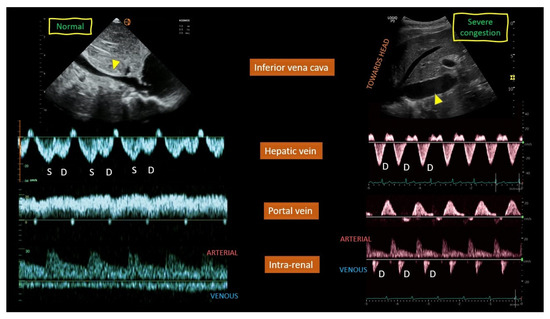

Background/Objectives: Heart failure (HF) causes systemic and regional haemodynamic alterations that extend beyond the heart, profoundly affecting splanchnic circulation. Venous congestion is a hallmark of heart failure (HF) and a major determinant of clinical deterioration and multiorgan dysfunction. The splanchnic venous system—comprising the portal, hepatic, and renal veins—acts as a key reservoir for intravascular volume redistribution. Conventional ultrasound (US), using grayscale and Doppler imaging, offers a direct, non-invasive approach to visualize these haemodynamic changes. This review, Part 1 of a two-part series, summarizes the current evidence and clinical applications of conventional US for assessing splanchnic, cardiac and pulmonary vascular alterations in patients with HF. Methods: A systematic review was performed in PubMed, Embase, and the Cochrane Library up to current date, following PRISMA 2020 guidelines. Eligible studies included adult human investigations evaluating splanchnic vascular changes in HF using B-mode, color Doppler, or pulsed Doppler ultrasonography. Exclusion criteria were pediatric, animal, or non-English studies and non-standard imaging methods. Data on ultrasonographic parameters, haemodynamic correlations, and prognostic value were extracted and qualitatively synthesized; Results: A total of 148 eligible studies (n ≈ 7000 patients) demonstrated consistent associations between HF severity and alterations in splanchnic, cardiac and pulmonary flow. Findings included increased bowel wall thickness, portal vein dilation with elevated pulsatility, and monophasic or reversed hepatic vein waveforms, all correlating with higher right atrial pressure and adverse clinical outcomes. The integration of these parameters into the Venous Excess Ultrasound (VExUS) framework enhanced detection of systemic venous congestion, in addition to the study of the cardiac and pulmonary circulation. Conclusions: Conventional ultrasound assessment of splanchnic vasculature provides valuable, reproducible insight into systemic congestion in HF. Incorporating hepatic and portal Doppler indices into standard evaluation protocols may improve risk stratification, optimize decongestion therapy, and guide management. Further prospective randomized and outcome-driven studies are required before VExUS-based therapeutic thresholds can be universally recommended and define prognostic thresholds. Full article

Figure 1